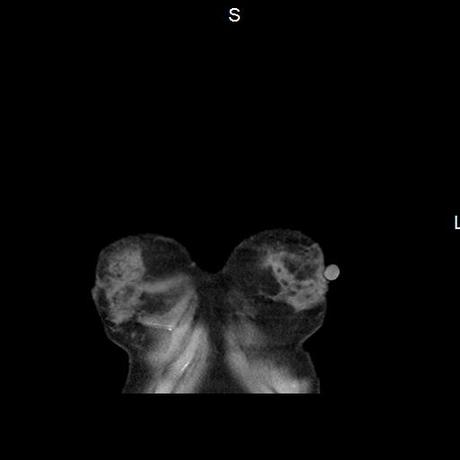

El parénquima pulmonar con areas parcheadas difusas en vidrio despulido combinadas con otras areas hipodensas de baja atenuación debidas a atrapamiento aéreo y engrosamiento intersticial y zonas de fibrosis de predominio en lóbulos medios e inferiores de ambos pulmones.

- LOS HALLAZGOS PUEDEN ESTAR EN RELACIÓN A NEUMOPATIA INTERSTICIAL PROBABLE ETIOLOGIA HIPERSENSITIVA VS AUTOINMUNE/BACTERIANA/FUNGICA.